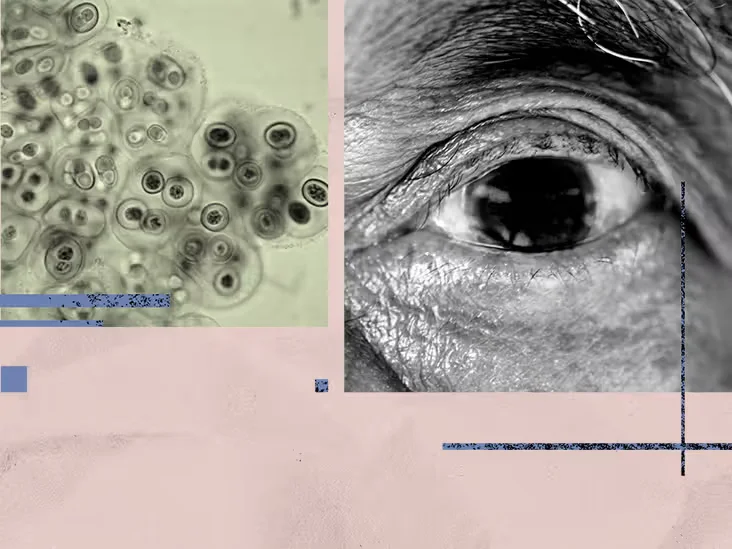

Eye-dwelling bacteria linked to Alzheimer's risk could aid early detection

A Nature Communications study found higher levels of the bacterium Chlamydia pneumoniae in retinal tissue of people with Alzheimer's disease, with greater bacterial burden associated with more severe cognitive decline. The findings, supported by lab and mouse models, suggest retinal infection and inflammation may reflect brain pathology and that APOE4 carriers had higher retinal bacterial levels, pointing to retinal imaging as a potential noninvasive biomarker and possible infection-targeted therapies.